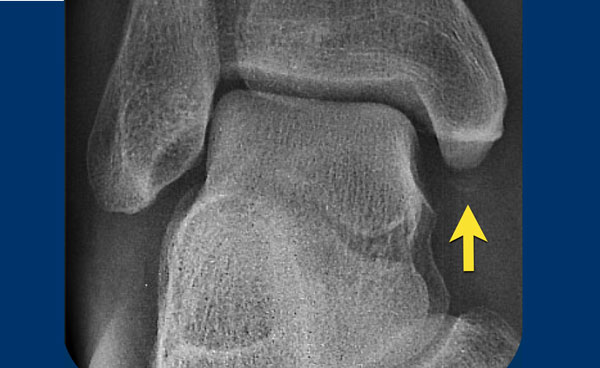

- Thoạt nhìn, có vẻ như chỉ có đơn thuần gãy mắt cá sau (tertius).

- Khi nhìn vào thuật toán, có thể thấy rằng gãy mắt cá sau có thể gặp trong gãy Weber B ở giai đoạn 3 và trong gãy Weber C ở giai đoạn 4.

Vì bệnh nhân này không có Weber B, đây phải là gãy xương Weber C. Gãy mắt cá sau đơn độc rất hiếm gặp và có lẽ không tồn tại. - Bây giờ chúng ta nhận ra phù nề phần mềm ở phía trong, đây là giai đoạn 1.

- Trên hình phóng to, chúng ta cũng nhận ra một mảnh gãy avulsion nhỏ.

Sau khi phát hiện giai đoạn 1 và 4 của cơ chế chấn thương kiểu Weber C, chúng ta có thể chắc chắn rằng cũng phải tồn tại giai đoạn 3, tức là gãy xương mác ở vị trí cao.